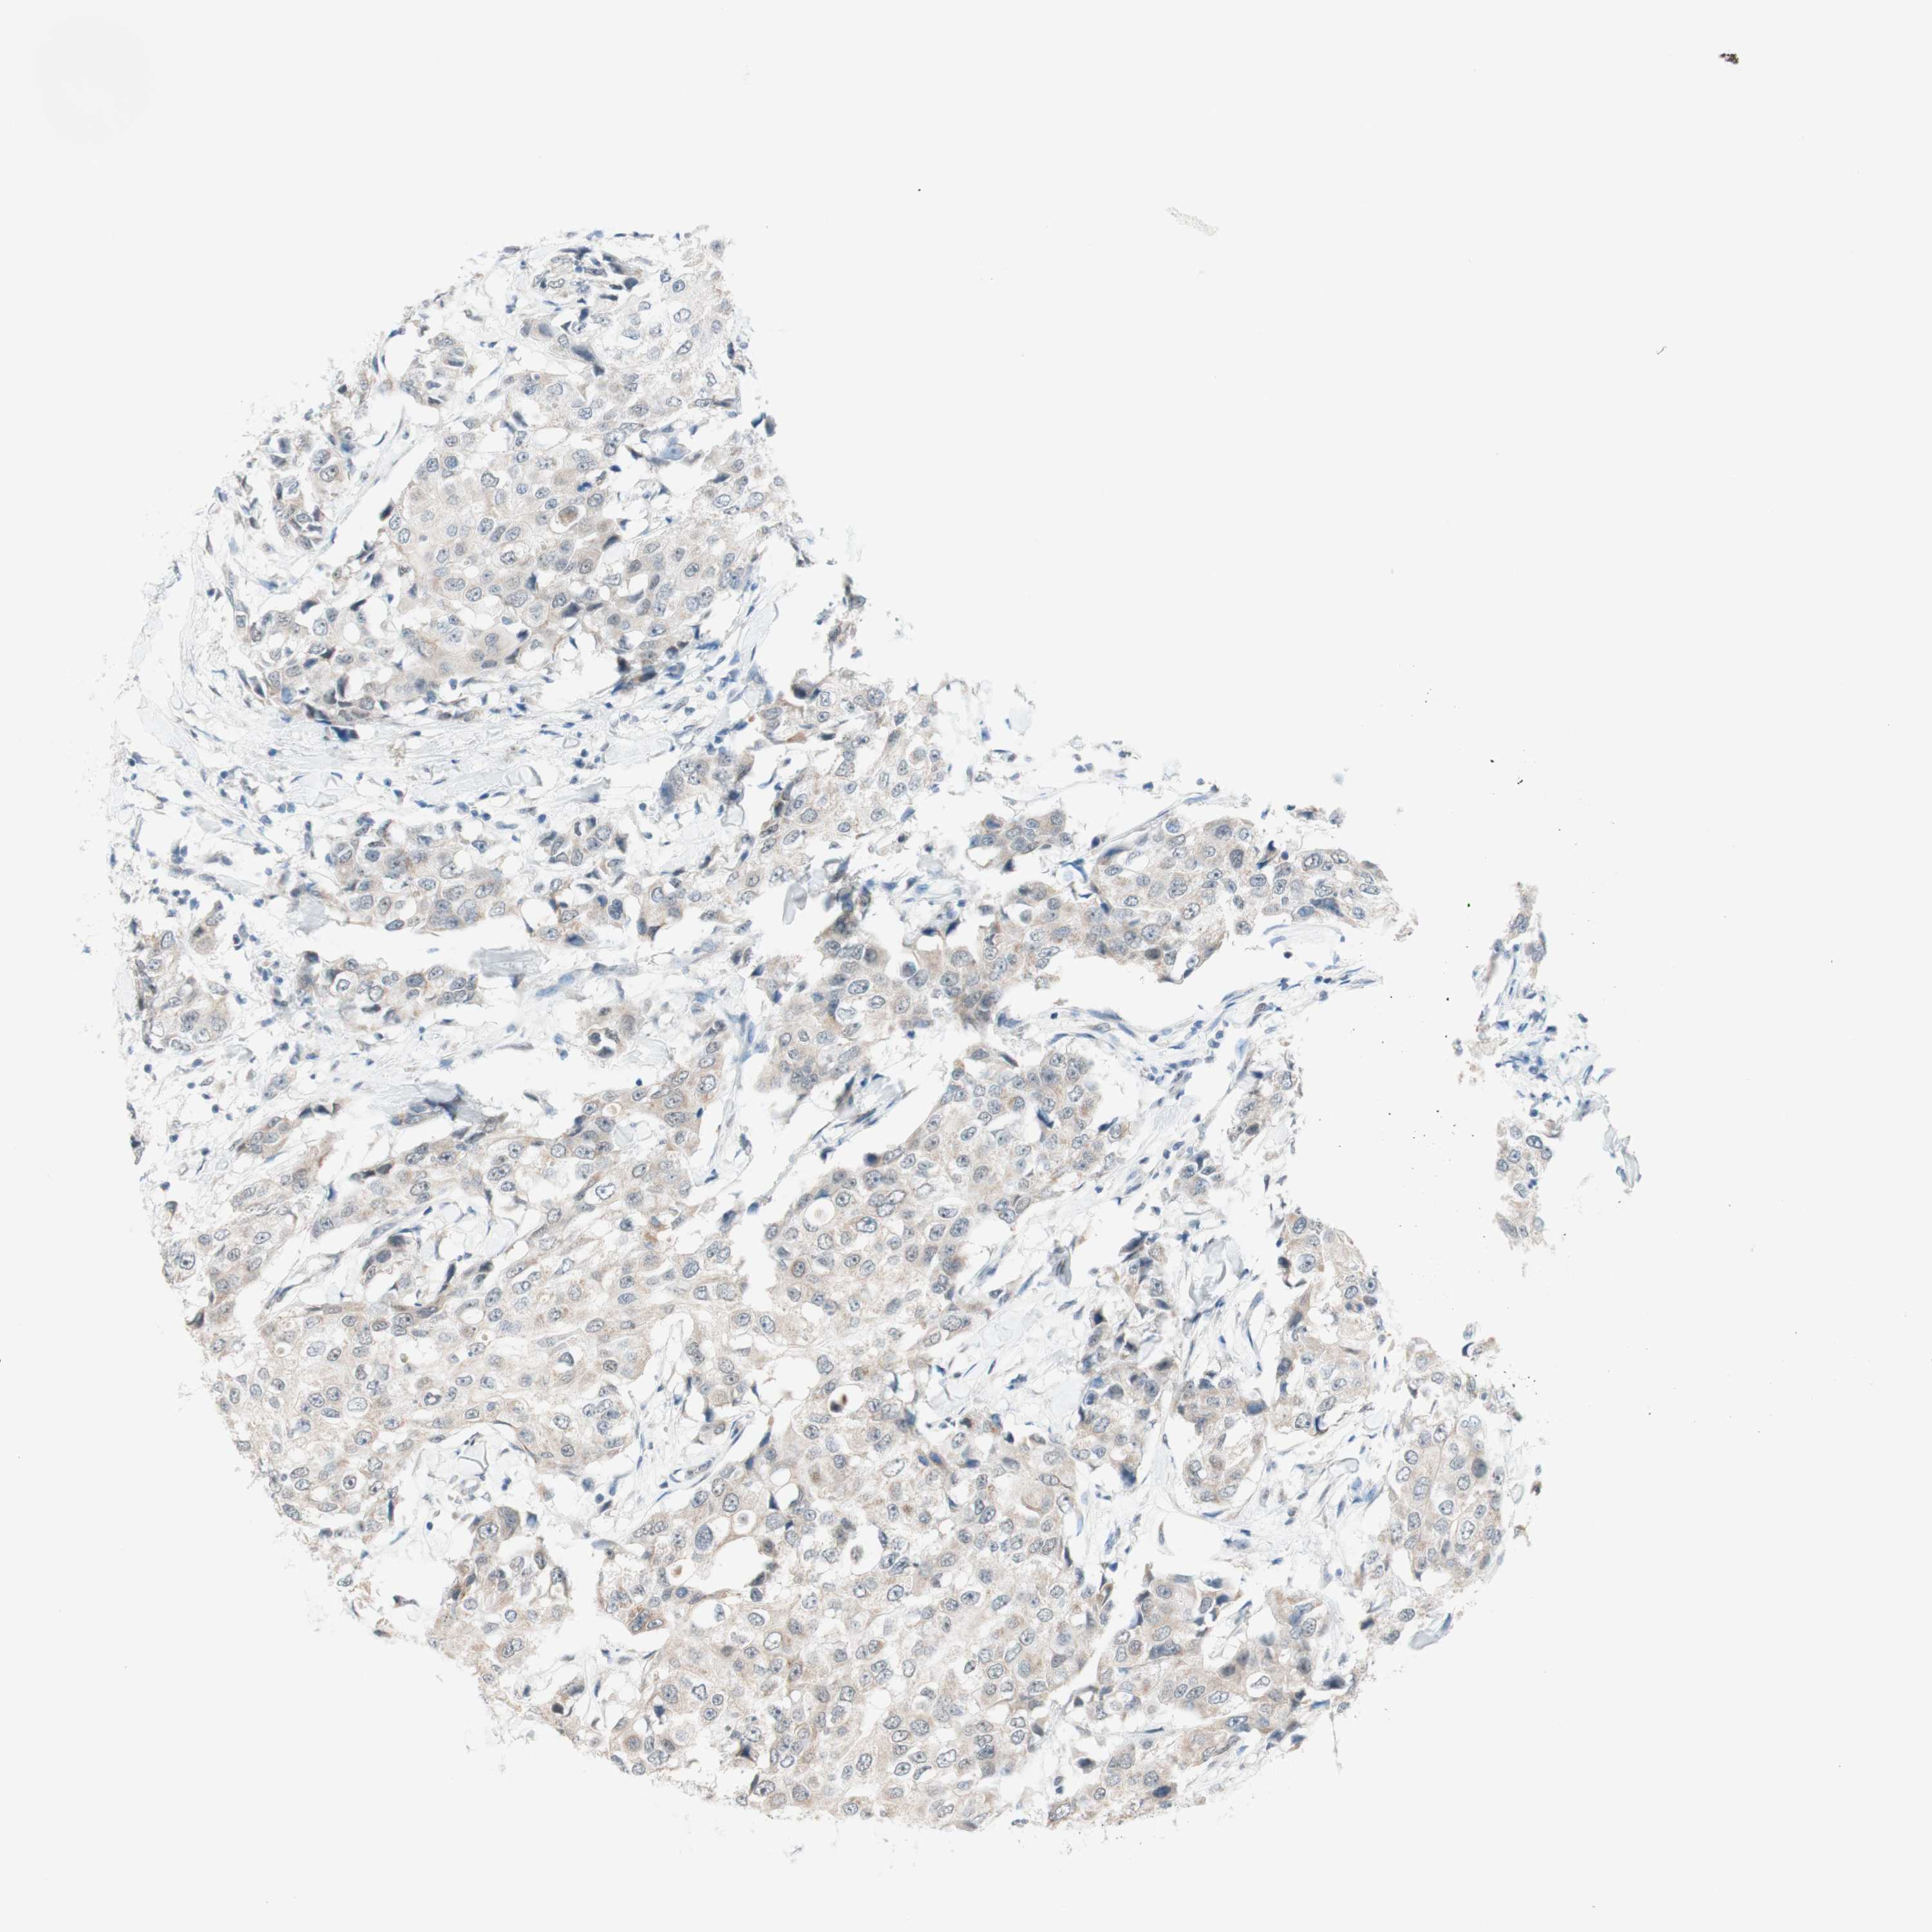

CANCER BREAST CANCER Show tissue menu

BRCA TCGA BRCA VALIDATION PROTEIN EXPRESSION

ANTIBODIES